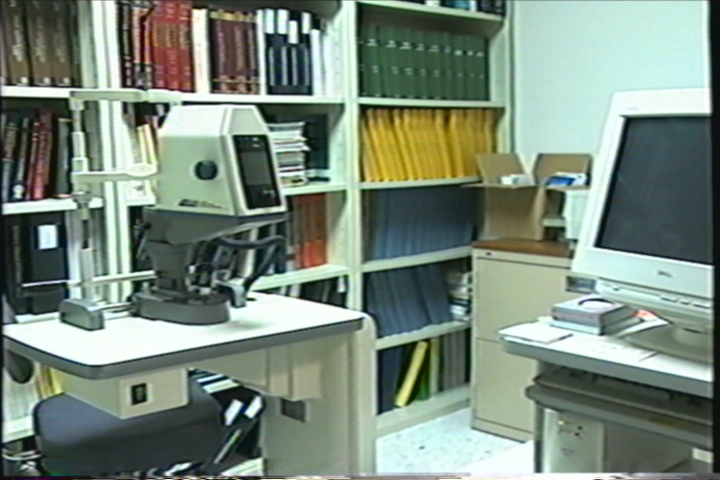

Ophthalmology Lab

Instruments in the Ophthalmology Lab acquired through the Lions Eye Research Foundation of New Jersey.